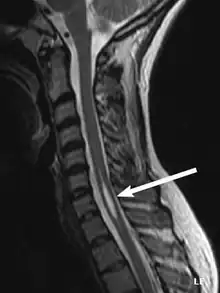

Physicians now use magnetic resonance imaging (MRI) to diagnose syringomyelia. The MRI radiographer takes images of body anatomy, such as the brain and spinal cord, in vivid detail. This test will show the syrinx in the spine or any other conditions, such as the presence of a tumor. MRI is safe, painless, and informative and has greatly improved the diagnosis of syringomyelia.[19]

The possible causes are trauma, tumors, and congenital defects. It is most usually observed in the part of the spinal cord corresponding to the neck area. Symptoms are due to spinal cord damage and include pain, decreased sensation of touch, weakness, and loss of muscle tissue. The diagnosis is confirmed with a spinal CT, myelogram or MRI of the spinal cord. The cavity may be reduced by surgical decompression.[23]